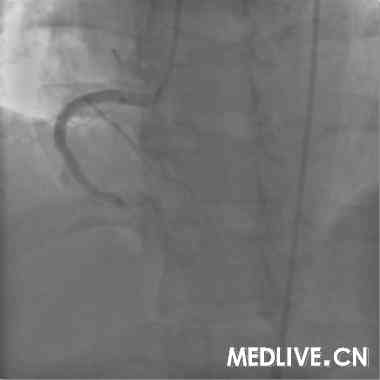

术前血管造影(附图):

冠造结果(图2-4):回旋支中段100%闭塞;右冠中段100%,并见大量血栓影;前降支中段不规则狭窄50%。结合临床,考虑右冠为急性心肌梗死相关冠脉,应首先对其进行急诊介入治疗。